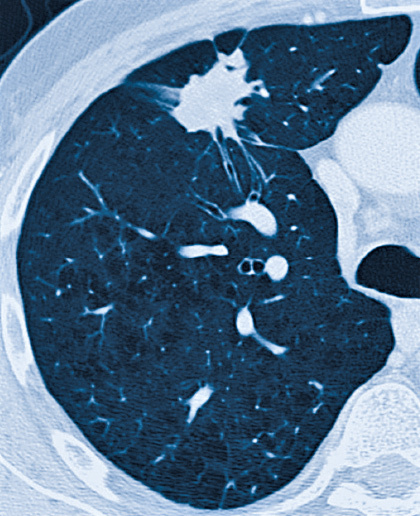

Der Atem wird immer flacher und setzt zuweilen aus. Bei Verdacht auf Lungenkrebs Bronchialkarzinom ergibt sich die erste Diagnose aus bildgebenden Untersuchungen wie Röntgenuntersuchungen oder einer Computertomographie CT der Lunge besonders wenn der Patient gleichzeitig über Symptome wie Husten blutigen Auswurf Atemnot oder auch Fieber und Gewichtsverlust klagt. Das führt unter anderem zu Schwäche Abgeschlagenheit Konzentrationsstörungen und Kopfschmerzen.

Anfangs oft keine oder nur unspezifische Beschwerden wie hartnäckiger Husten Brustschmerzen und Abgeschlagenheit. Wenn der Tumor die Brustwand angreift können dauerhafte unablässige Brustschmerzen auftreten. Bei Verdacht auf Lungenkrebs beginnt der Arzt die Diagnose in der Regel mit bildgebenden Untersuchungen wie Röntgenuntersuchungen oder einer Computertomographie CT der Lunge besonders wenn der Patient regelmäßig raucht und gleichzeitig über Symptome wie Husten blutigen Auswurf Atemnot Fieber und Gewichtsverlust klagt.